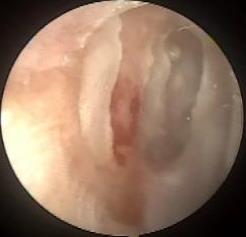

摘要:目的 探讨耳内镜下耳屏软骨-软骨膜鼓膜修补术后的短期疗效。方法 回顾性分析2019年9月-2022年8月该院收治的78例鼓膜穿孔患者的临床资料,患者均采用耳内镜下鼓膜修补术。术后随访3个月,观察鼓膜形态和穿孔愈合情况,记录内镜图像、干耳时间、术前术后听力及耳鸣情况,以及外耳道狭窄等并发症的发生率。结果 术后3个月,鼓膜穿孔愈合率为97.44%(76/78),愈合良好,平均气导听阈较术前明显改善,气骨导间距较术前明显缩小,耳鸣较术前明显改善,差异均有统计学意义(P<0.05)。干耳时间为(4.21±1.12)周。术后出现肉芽5例,再穿孔2例,真菌感染2例,术腔感染、耳屏感染、外耳道狭窄和切口瘢痕各1例,所有患者术后均未发生面神经麻痹和感音神经性聋等严重并发症。结论 耳内镜下耳屏软骨-软骨膜鼓膜修补术是一种安全、有效的手术方法。根据术后愈合规律、内镜下鼓膜和外耳道形态特征,可为鼓膜修补术后正常中耳转归和并发症的诊疗,提供临床参考。